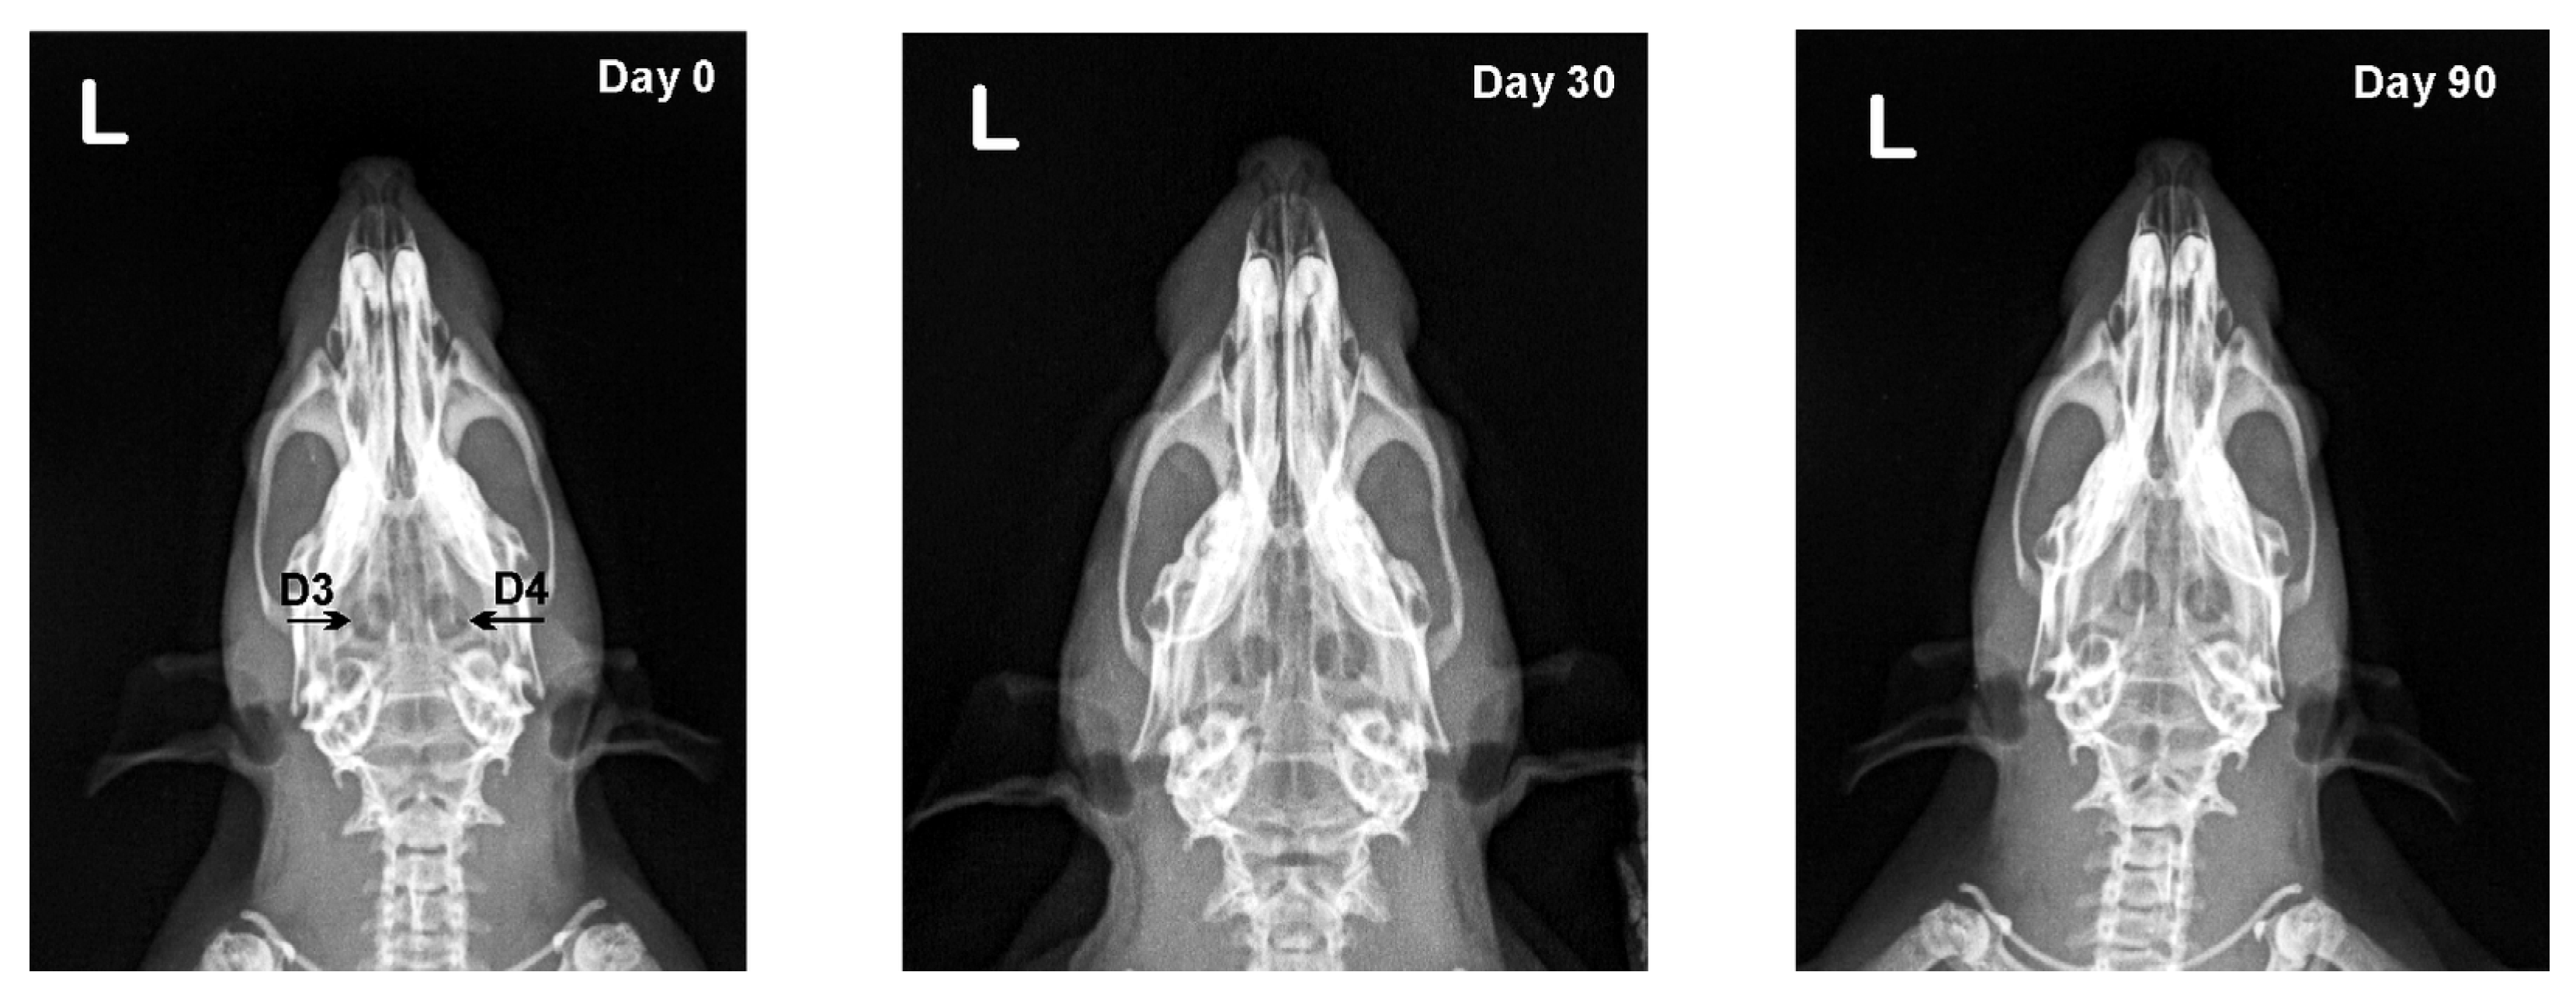

3.2. X-ray Results

| Defect | Day 0 | Day 30 | Day 90 |

|---|---|---|---|

| D1 | 0.92 ± 0.02 | 0.92 ± 0.03 | 0.93 ± 0.03 |

| D2 | 0.93 ± 0.02 | 0.93 ± 0.04 | 0.95 ± 0.04 |

| D3 | 0.92 ± 0.02 | 0.91 ± 0.03 | 0.90 ± 0.03 |

| D4 | 0.93 ± 0.01 | 0.92 ± 0.02 | 0.90 ± 0.02 * |

| D1 | 0 (0–0) | 1 (0–2) **# | 2 (1–2) ** |

| D2 | 0 (0–0) | 2 (2–3) *** | 2 (2–3) *** |

| D3 | 0 (0–0) | 0 (0–2) | 0 (0–2) |

| D4 | 0 (0–0) | 0 (0–2) | 1 (0–2) |